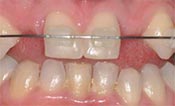

安卓健临床案例分享

安卓健种植产品销往全球100多个国家精密工程CFDA

权威认证,可放心使用。安卓健种植体手术程序简单,

更少创伤,更快恢复,更加安心。